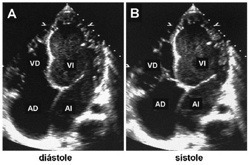

Es la prueba diagnóstica más valiosa y se ha de realizar siempre que se sospeche esta enfermedad.

Los hallazgos principales son los siguientes:

• Hallazgo típico: dilatación de las cavidades afectadas y su forma esferoidal, especialmente del ventrículo izquierdo.

• Las paredes están adelgazadas.

• Disminución difusa de la función contráctil.

• Pese a que la fracción de eyección suele estar baja, el gasto cardíaco en estos pacientes puede ser normal. Esto se debe a que los volúmenes de eyección están muy aumentados y además existe una taquicardia compensadora.

Stacks Image 3263

Ecocardiografía 2D. Marcada dilatación de las cavidades cardíacas.